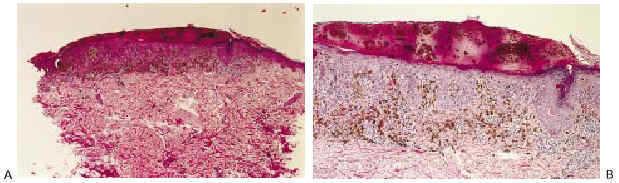

El estudio histopatológico mostró una tumoración simétrica, compuesta por melanocitos maduros fusiformes intensamente pigmentados, dispuestos en nidos y en fascículos interconectados en la epidermis y en la dermis papilar. Se acompañaban de numerosos melanófagos, dando una imagen típica de melanosis en banda en la dermis superficial (Fig. 3). El diagnóstico histológico resultante fue de nevus fusocelular pigmentado (nevo de Reed).

FIG. 3--A: Panorámica histológica. B: Presencia de abundantes melanófagos dando la imagen típica de melanosis «en banda» en la dermis superficial. Melanocitos fusiformes pigmentados dispuestos en nidos y fascículos interconectados en la epidermis y la dermis papilar. C: Correlación dermatoscópico-histológica: tecas compactas de melanocitos fusiformes situados en los extremos de la lesión que se corresponden con las extensiones periféricas digitiformes observadas en la dermatoscopia.